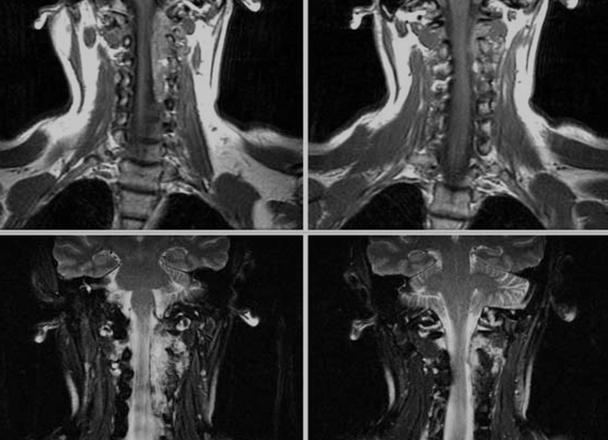

Визуализировать органы шеи и мягкие ткани очень сложно на рентгене, для этого применяются контрасты, да и то диагноз выставляют косвенно. Революционным открытием в этом направлении стало МРТ (магнитно-резонансная томография), она позволяет увидеть патологию мягких тканей. У человека в области шеи, головы есть много органов, сосудов, нервов, которые необходимо визуализировать, чтобы установить точный диагноз. Проведенное МРТ шейного отдела, головы позволяет это сделать наиболее качественно и оптимально.